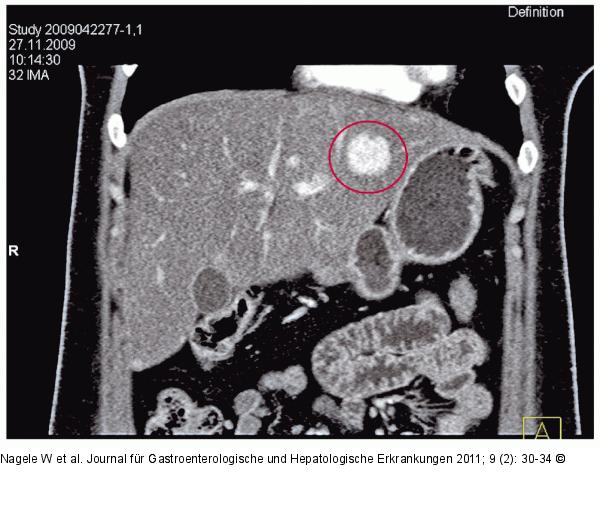

Abbildung 2: CT des Oberbauchs mit Kontrastmittel CT des Oberbauchs mit Kontrastmittel: In der portalvenösen Phase homogene Kontrastmittelanfärbung eines Pelioseherdes im Lebersegment 2. Ein weiterer, kleiner, homogen angefärbter Herd zeigt sich am Unterrand der Leber. |